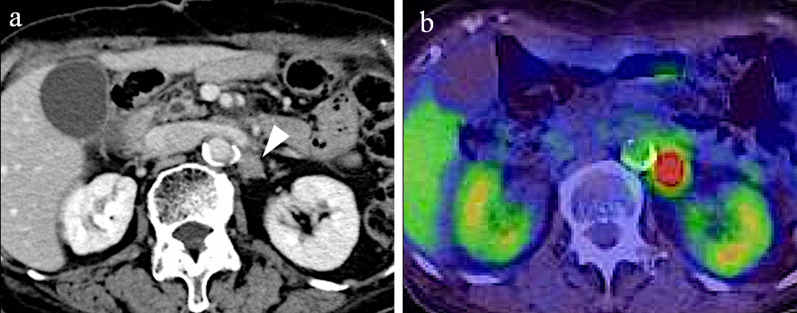

Fig. 3.

a Contrast-enhanced CT and b fluorodeoxyglucose-positron emission tomography/CT at recurrence of cancer appeared in No. 16b1. The size was 14.6 mm

One year after gastrectomy, a CT scan revealed swelling of the paraaortic (No. 16b1 LN) (Fig. 3a) and left supraclavicular LNs. In addition, CA19-9 remained high at 40.1 U/mL, CEA elevated to 6.1 ng/mL, and a positron emission tomography/CT scan showed abnormal accumulation of fluorodeoxyglucose in No. 16b1 LN (Fig. 3b). For the recurrent gastric cancer, S-1 plus oxaliplatin (SOX) therapy (S-1 80 mg/m2/day, oxaliplatin 100 mg/m2) was initiated as the first-line chemotherapy. After the seventh course of SOX therapy, the supraclavicular LN disappeared, but the paraaortic LN became enlarged (Fig. 4a). Therefore, PTX plus RAM therapy (PTX 80 mg/m2 and RAM 8 mg/kg) was initiated as the second-line regimen (Fig. 5). After three courses of PTX plus RAM therapy, CT revealed shrunken paraaortic LN (Fig. 4b), and PTX caused severe adverse effects, including grade 3 neutropenia and grade 2 peripheral neuropathy. The dose of PTX was reduced to 60 mg/m2 in the third course, and PTX was discontinued from the fourth course. CEA elevated to 11.2 ng/mL, but the size of paraaortic LN gradually shrank and CA19-9 decreased to 18.6 U/mL at the fifth course of RAM monotherapy. However, 3 + proteinuria and hypertension occurred before the sixth course of RAM monotherapy. The RAM was reduced to 6 mg/kg, and the patient observed a drug withdrawal period of 7 weeks. Because the size of paraaortic LN was enlarged after withdrawal period (Fig. 4c), 6 mg/kg of RAM monotherapy was resumed. After resuming RAM administration, the paraaortic LN significantly shrank again (Fig. 4d). However, 4 + proteinuria occurred and the urine protein–creatinine ratio was 5.29. Thus, RAM was withdrawn again, and regular CT and urinalysis were scheduled with sufficient informed consent. During the 14-month withdrawal period, hypertension was controlled by a calcium blocker, proteinuria remained at 2 + , and LN enlargement was not observed. Since the paraaortic LN was enlarged to 14 mm, RAM (8 mg/kg) was administered again. Unfortunately, the patient had a femoral fracture shortly after resumption and needed further drug withdrawal. During this period, the paraaortic LN grew to 14.8 mm. After the patient recovered, RAM was readministered, and the paraaortic LN shrank to 8.7 mm again. RAM monotherapy was continued while carefully observing adverse events, such as proteinuria and hypertension, 57 months after the conversion surgery.